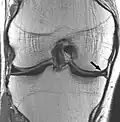

Musculoskeletal

Applications in the musculoskeletal system include spinal imaging, assessment of joint disease, and soft tissue tumors.[44] MRI techniques can also be used for diagnostic imaging of systemic muscle diseases including genetic muscle diseases.[45][46]

| Proton density weighted | PD | Long TR (to reduce T1) and short TE (to minimize T2).[70] | Joint disease and injury.[71]